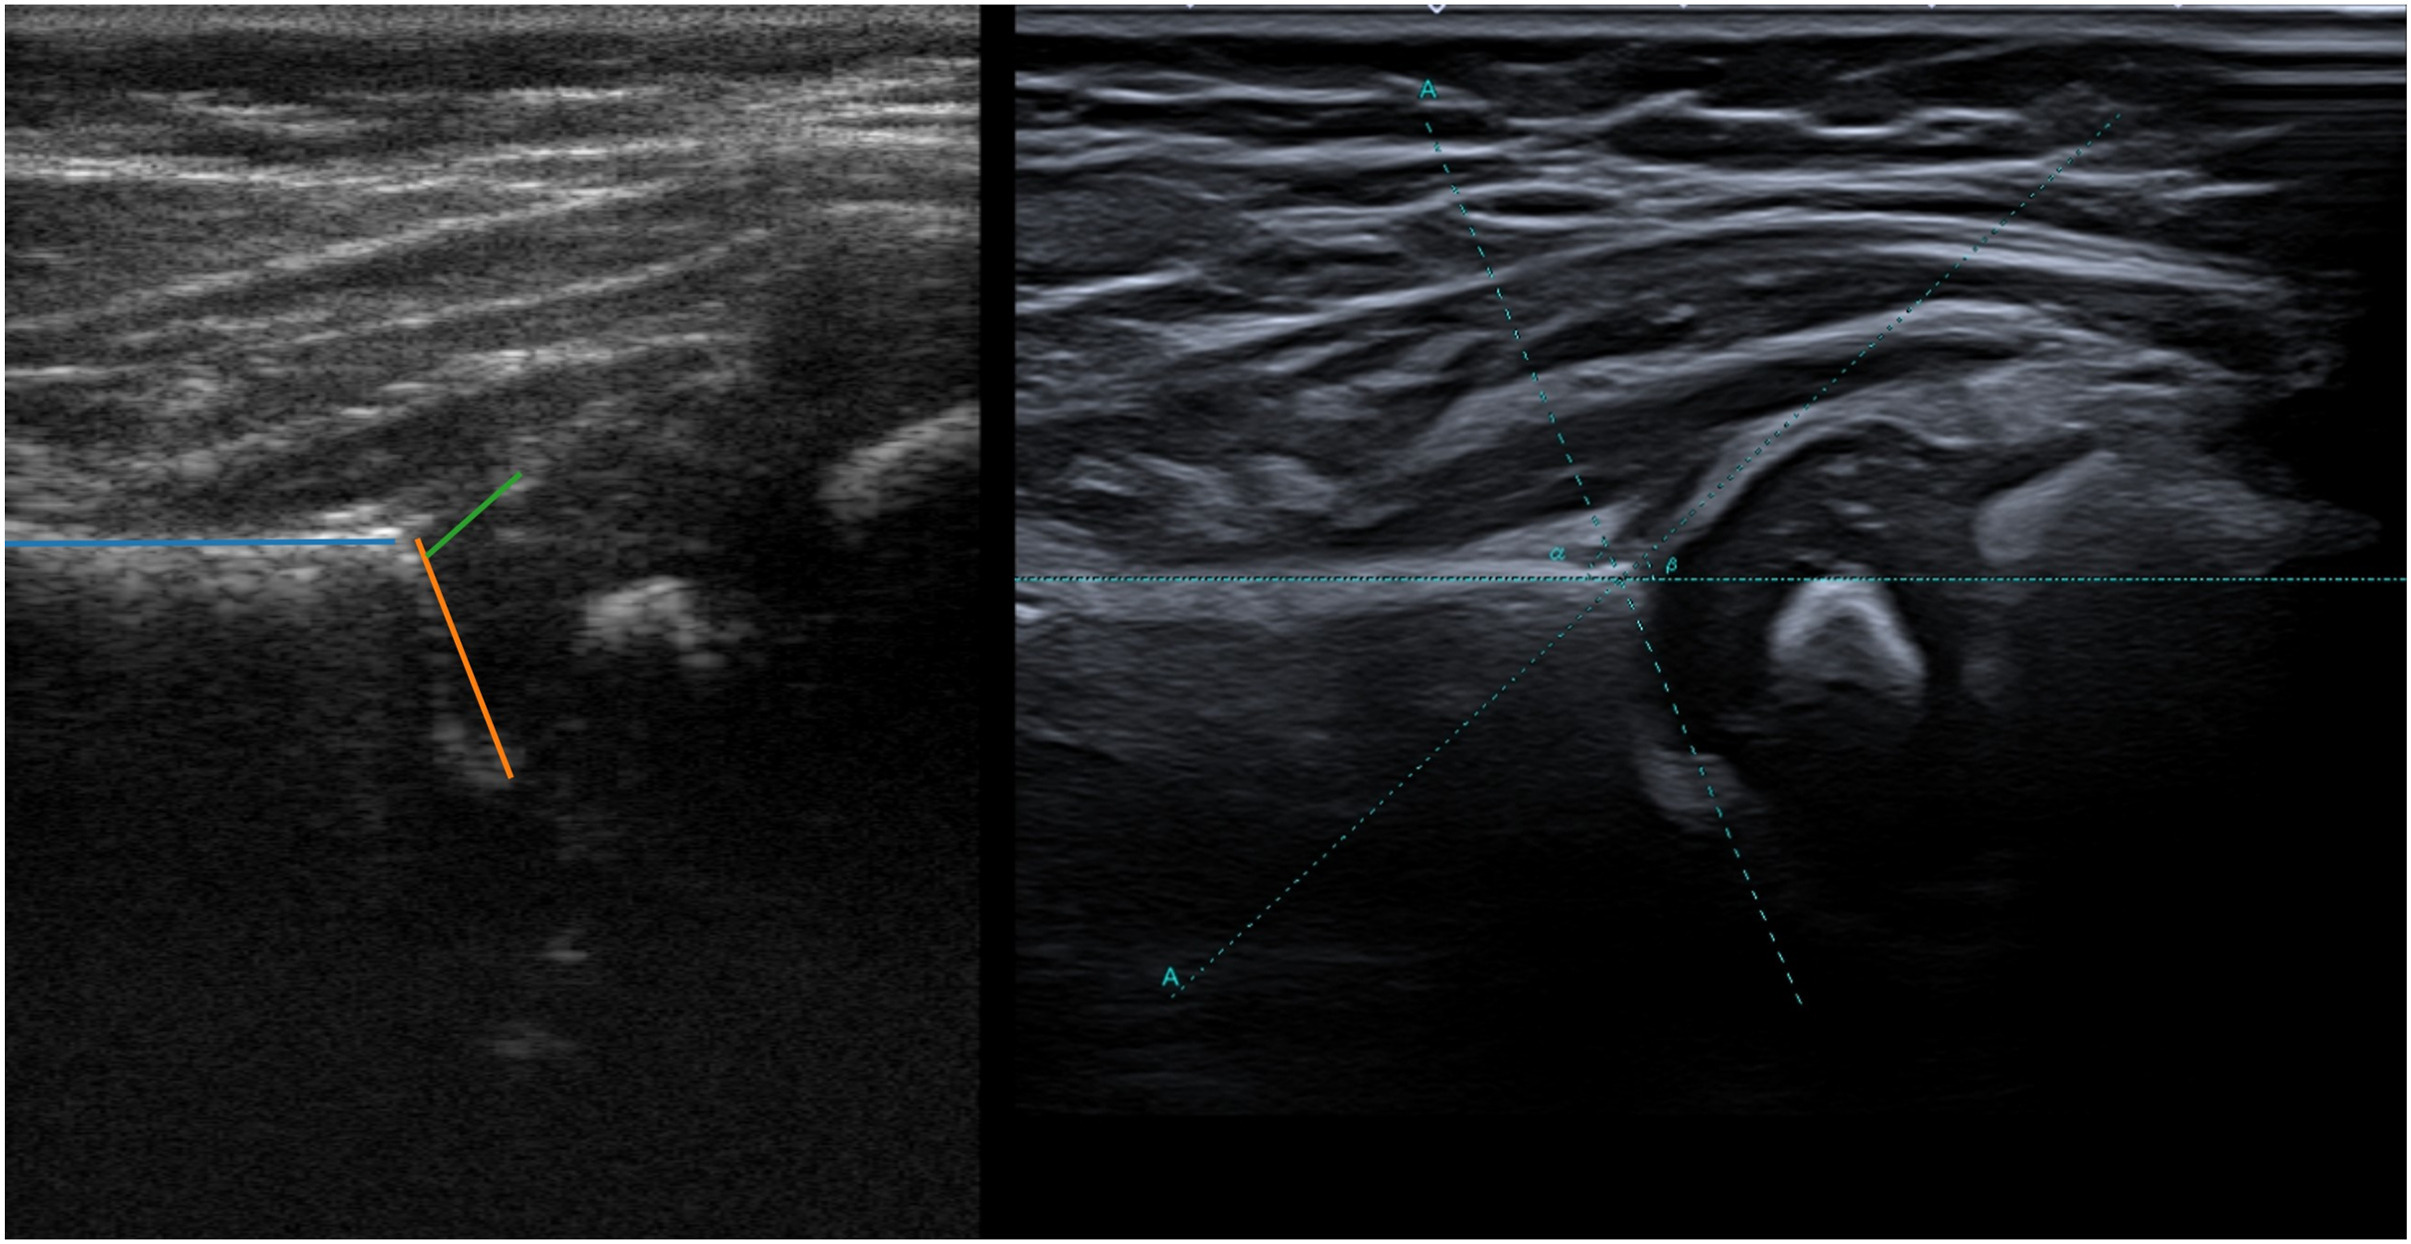

Our feasibility study [Kersten et al. 2025] shows that a radiologist is able to rule-out DDH in 82 % of hips using an AI-assisted ultrasound acquired by a novice user with 1 hour of training. Below shows an example of an ultrasound image acquired by the novice user within this study.

Figure: Left hip of a female infant at the age of 15 weeks, term 40 + 0 weeks, and reason for referral was a family history positive for DDH. Left image: selected frame of acquisition of novice user with α-angle 69°, β-angle 41° and diagnosis ‘no DDH’. Right image: ground truth ultrasound by a radiologist with α-angle 67°, β-angle 43° and diagnosis ‘no DDH’.